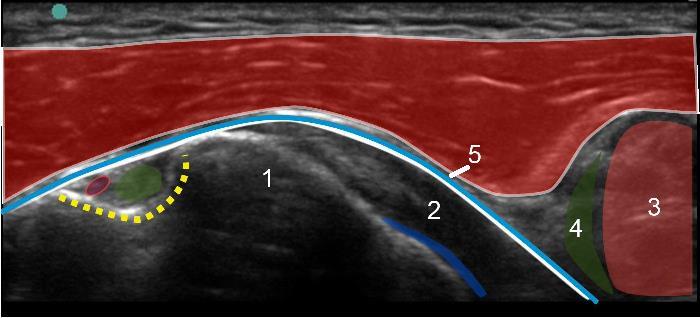

1. Lesser Tuberosity

2. Subscapularis Tendon

3. Coracobrachialis

4. Short Head of the Biceps Tendon

5. Subacromial Subdeltoid Bursa